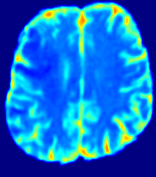

Figure 3: PIANO feature maps for one stroke patient, where the lesion is located in the left hemisphere. Top row: segmented stroke lesion region (white) on different slices, obtained from ISLES 2017. The corresponding slices for the PIANO feature maps are shown in the following rows.

For a better insight into an estimated velocity field 𝐕𝐕{\bf{V}} and diffusion field 𝐃𝐃{\bf{D}}, we compute the following maps: (1) 𝐕rgbsubscript𝐕𝑟𝑔𝑏{\bf{V}}_{rgb}: Color-coded orientation map of 𝐕=(Vx,Vy,Vz)T𝐕superscriptsuperscript𝑉𝑥superscript𝑉𝑦superscript𝑉𝑧𝑇{\bf{V}}=(V^{x},V^{y},V^{z})^{T}, obtained by normalizing 𝐕𝐕{\bf{V}} to unit length and mapping its 3 components to red, green, blue respectively; (2) 𝐕2subscriptnorm𝐕2\|{\bf{V}}\|_{2}: 222 norm of 𝐕𝐕{\bf{V}}; (3) D𝐷D: scalar field in Eq. 5.

Fig. 3 and Fig. 4 show the PIANO feature maps estimated from two ISLES 2017 patients: all are highly consistent with the lesion in both cases. Details of the blood flow trajectories are revealed in 𝐕rgbsubscript𝐕𝑟𝑔𝑏{\bf{V}}_{rgb} by the ridged patterns and the sharp changes of colors in the unaffected (right) hemisphere, while the flat patterns appearing within the lesion provide little directional information about the velocity and indicate low velocity magnitudes. Velocity magnitudes are more directly visualized via 𝐕2subscriptnorm𝐕2\|{\bf{V}}\|_{2}, from which one can easily locate the lesion where 𝐕2subscriptnorm𝐕2\|{\bf{V}}\|_{2} is low. D𝐷D also indicates lower diffusion values in the lesion, though with less contrast potentially due to the fact that it captures the accumulated effect of CA diffusion at the voxel-level.